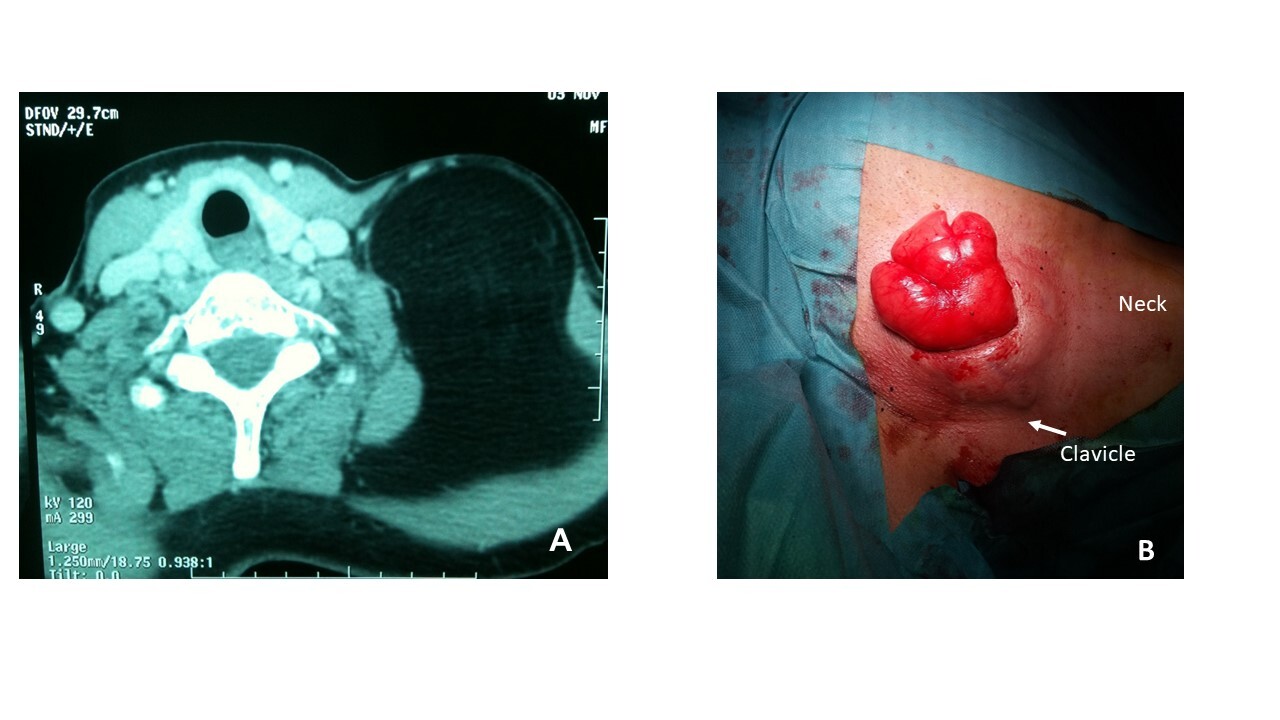

A 55-year-old female patient without previous pathological history was referred to our department with a 10-year history of a large and slowly progressive left-sided cervical mass. Physical examination revealed a 14 x 11-cm well-defined subcutaneous, soft in consistency, mobile mass on the lower third of the lateral neck on the left side and of the supraclavicular area without a slight superficial venous ectasia or ulceration. The neck and chest computed tomography (CT) scan demonstrated a large well-defined homogenous fat density mass measuring 18 x 10 cm occupying the left lower part of the neck and supraclavicular fossa (Figure 1a). There were no signs of cervical or chest wall invasion. Giant lipoma was diagnosed based on the radiological findings; no biopsy was undertaken because of the possible complete resection of the mass.

Under general anesthesia, the neck and anterior chest were exposed and accessed via a transverse skin incision (Figure 1b). Intraoperatively, the mass was well-encapsulated with minimal adhesions without any regional involvement or evident infiltration. Hemostasis was achieved with electrocautery and ligature of several veins, and a radical resection was performed.